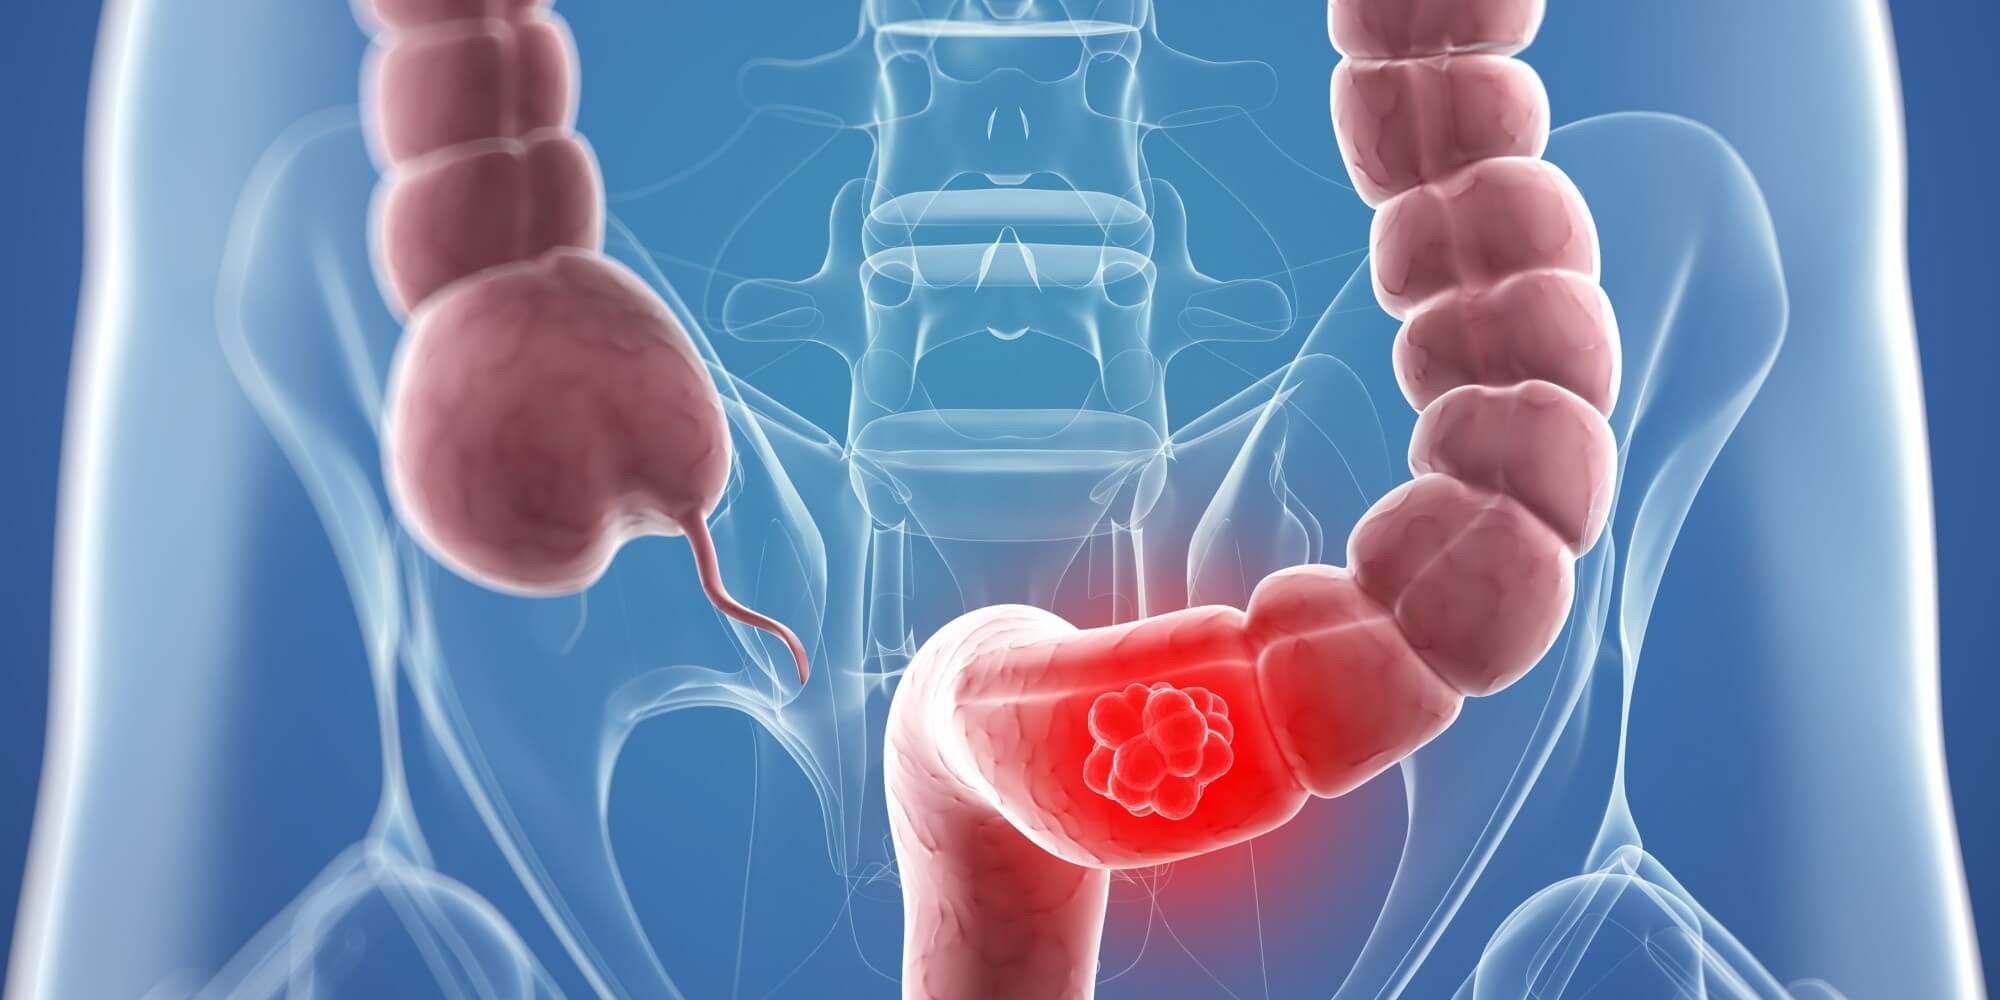

El Cáncer de Colon o Cáncer Colorrectal es un tumor maligno que aparece inicialmente en el colon o el recto y posteriormente puede invadir otras partes del cuerpo, como la vejiga, la matriz, intestinos, los pulmones, el hígado, etc. Es una enfermedad mortal si no se trata a tiempo. Tanto en México como a nivel mundial, es el tercer tipo de cáncer más frecuente en adultos. Además, el Cáncer de Colonpuede aparecer en cualquier persona ya que de cada 10 pacientes, en 9 no hay ningún antecedente de cáncer en la familia.

Al inicio, los pacientes no tienen síntomas. Después aparece sangrado al evacuar (de color rojo obscuro y mezclado dentro de la materia fecal), alteración de los hábitos usuales de la defecación (ya sea estreñimiento o diarrea, o ir mas menos frecuente al baño de lo usual, o hacer del baño un día si y un día no cuando antes iba del diario, o, por el contrario, hacer diario del baño cuando antes solo iba una vez cada tener día), evacuaciones delgadas y aplanadas o disminución de peso de forma inexplicable. El dolor es un síntoma que aparece mucho después y al principio es tan leve que no se le da importancia; sólo cuando el problema está muy avanzado el dolor ya es intenso.

Como los síntomas no siempre son muy evidentes, se necesita revisar por dentro todo el colon y el recto mediante una colonoscopía (aunque también podría hacerse un colon por enema). Si se observa alguna lesión sospechosa, se debe tomar una muestra para mandarla a analizar (biopsia). En caso de que se corrobore el cáncer, es necesario realizar varios estudios para determinar que tan avanzado está (Tomografía, Ultrasonido, Antígeno Carcino-Embrionario, etc.).